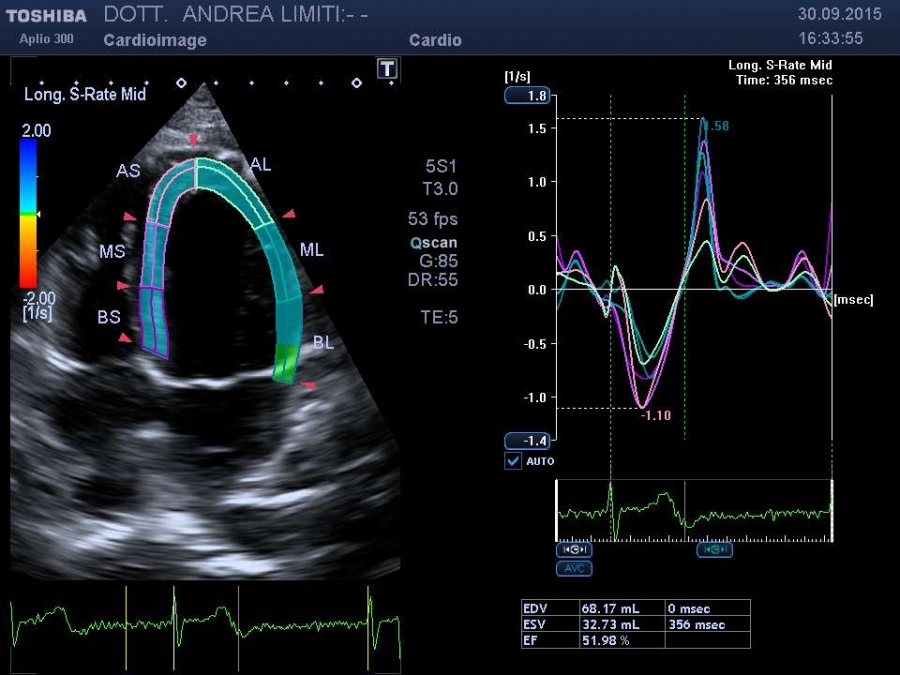

La visita cardiologica, l’Elettrocardiogramma e l’Ecocardiogramma bidimensionale Color Doppler transtoracico consentono di acquisire una ricchezza di informazioni sullo stato anatomico e funzionale del cuore di livello molto elevato che spesso consentono un primo accurato inquadramento dei problemi cardiologici del paziente. E’ importante tuttavia sapere che, anche con gli apparecchi più avanzati, l’ecocardiografia non offre una valutazione diretta dello stato delle coronarie e quindi l’esame non può essere discriminante per la valutazione di sospetti dolori cardiaci.